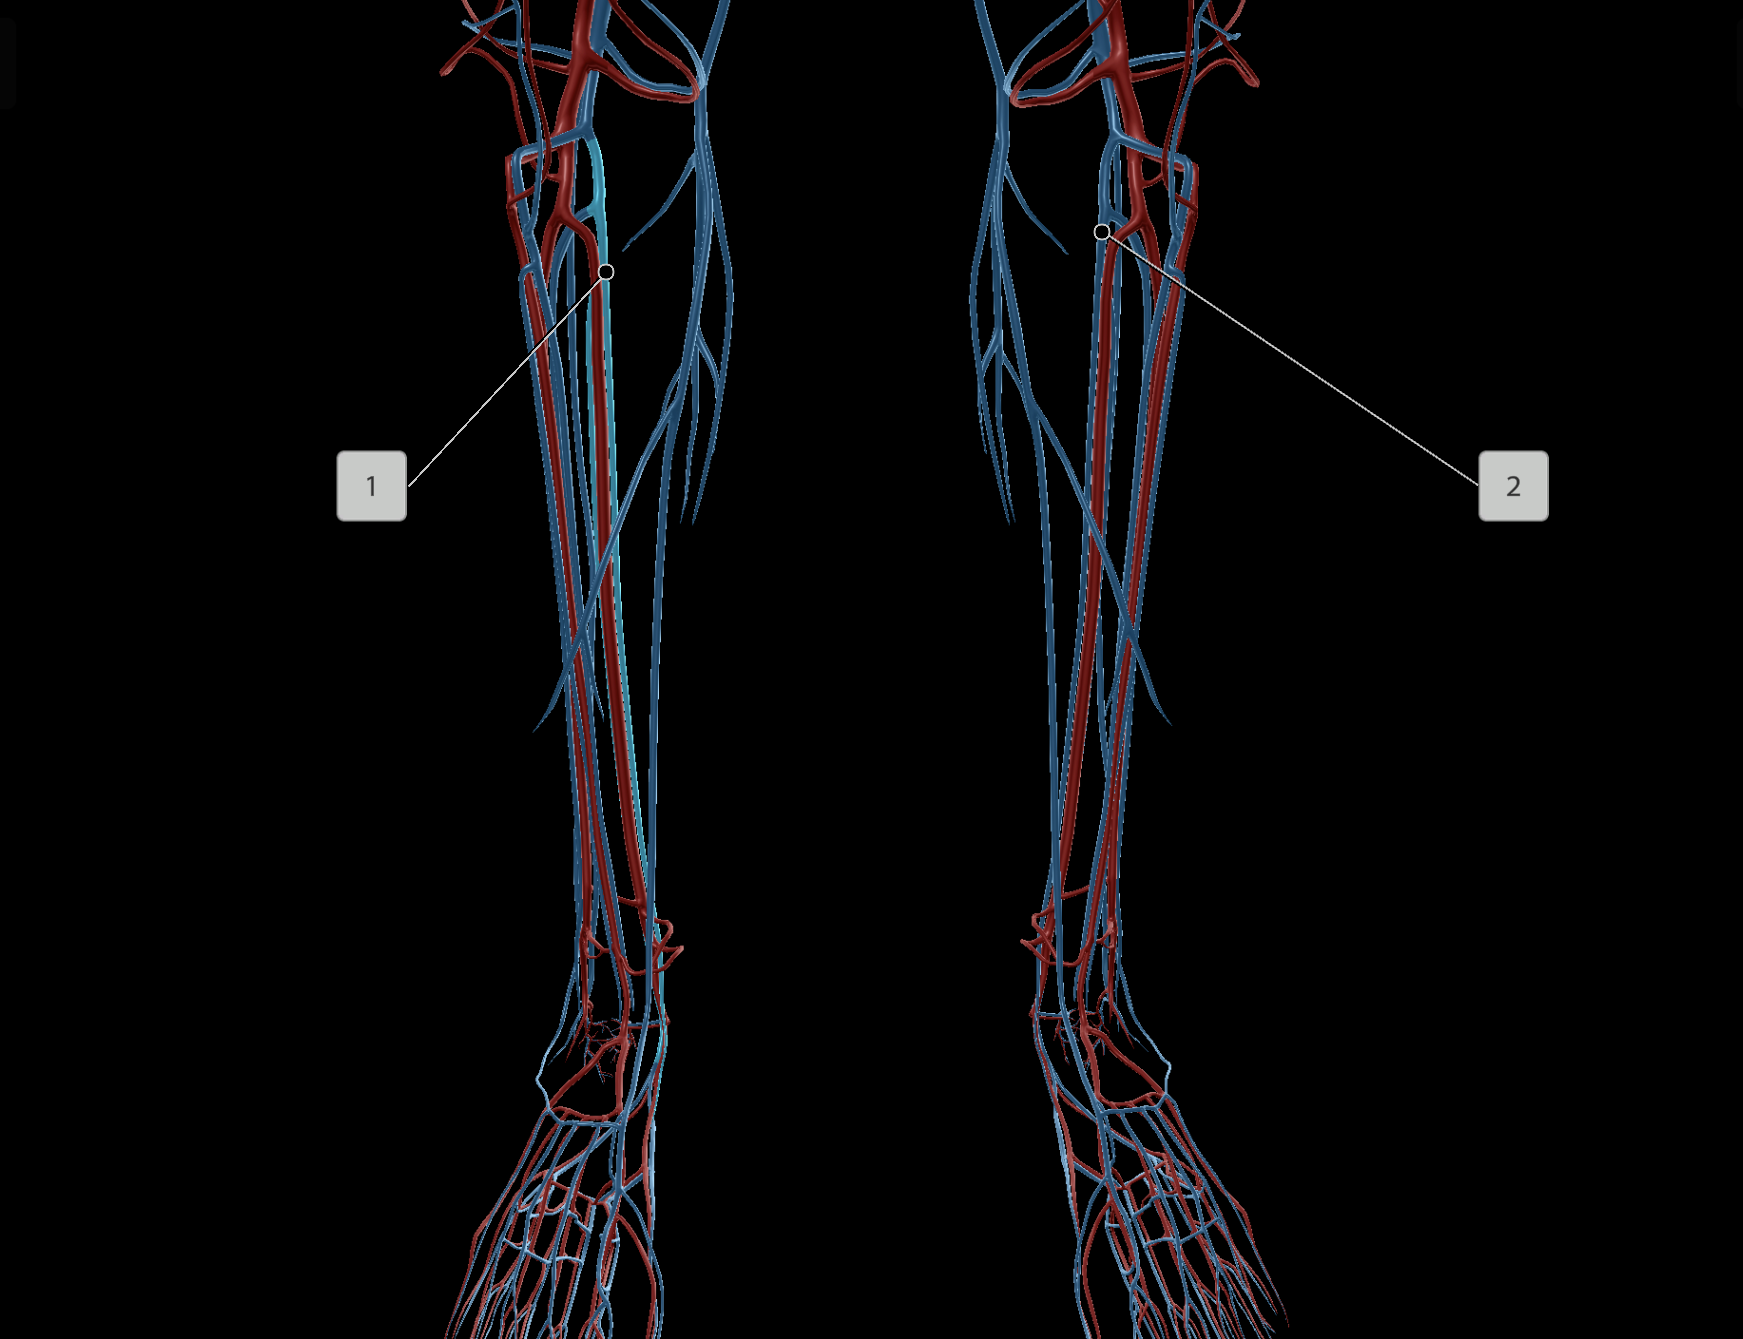

Anterior Tibial Artery

Posterior Tibial Artery

Dorsal Pedis Artery

Anterior Tibial Vein

Posterior Tibial Vein

Great Saphenous Vein

Peroneal Artery